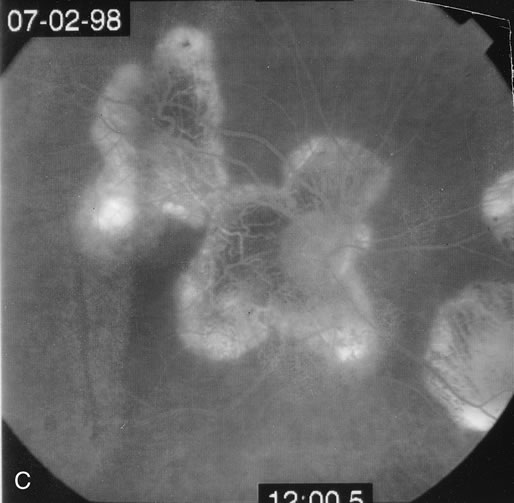

Some patients present with subretinal bands that extend between chorioretinal scars. In addition there may be initial active yellow choroidal lesions that subsequently become atrophic. Vitreous cells are usually present although they may be few and difficult to detect. Visual acuity loss in these cases may be due to active choroidal neovascularization, subretinal bands under the fovea, or from cystoid macular edema. The vast majority of affected patients are women with a mean age of 27 years and both eyes are usually involved. The affected individuals tend to be myopic.49 The age range is from 6 years to 76 years and there is no racial predilection.40 Whether it is a separate disease or a more severe form of multifocal choroiditis is controversial (Figs. 10 and 11). Aggressive therapy is warranted because it has a poorer prognosis than most cases of multifocal choroiditis. This syndrome has been called either diffuse subretinal fibrosis or progressive subretinal fibrosis syndrome.

Fig. 10. A. Fundus photograph showing the subretinal fibrosis extending from the disc to the periphery in a case of diffuse subretinal fibrosis. B. Fundus photograph showing the marked fibrosis in the midperiphery. C. Multifocal choroiditis type lesions noted in the inferior retina.